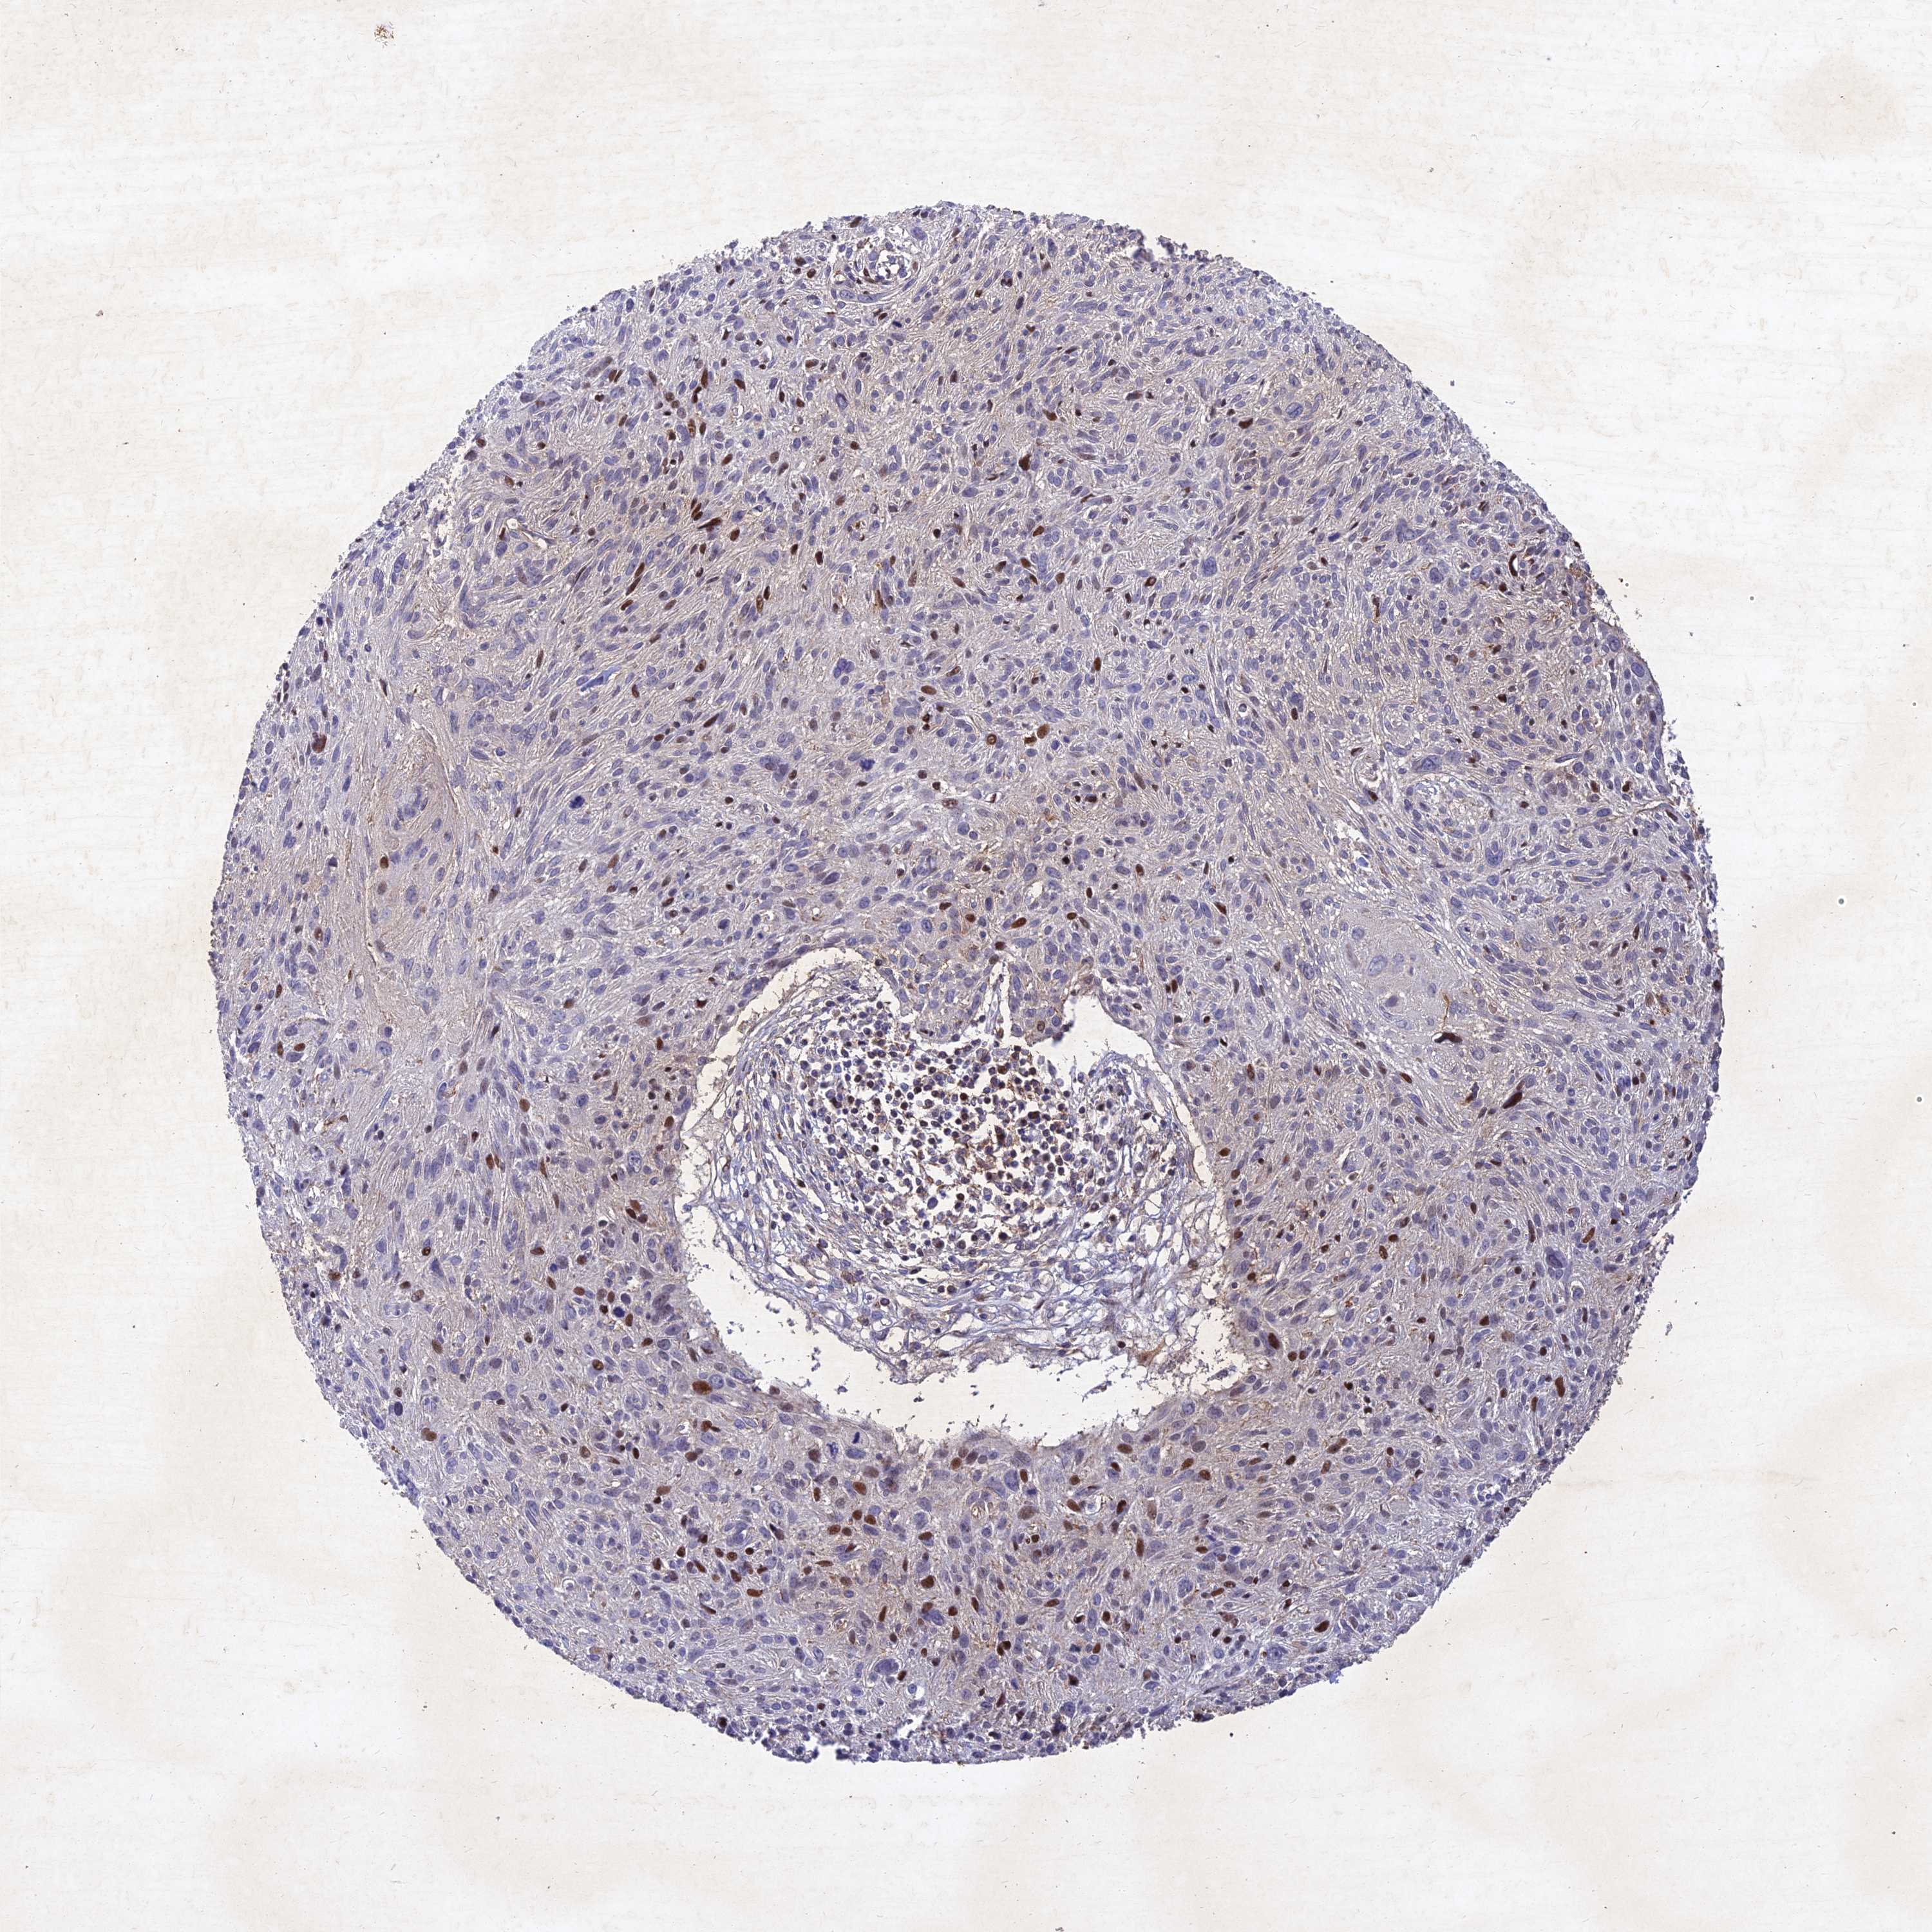

CERVICAL CANCER - Protein expressioni

A mouse-over function shows sample information and annotation data. Click on an image to view it in a full screen mode. Samples can be filtered based on level of antibody staining by selecting one or several of the following categories: high, medium, low and not detected. The assay and annotation is described here.

Note that samples used for immunohistochemistry by the Human Protein Atlas do not correspond to samples in the TCGA dataset.

Antibody stainingi

Antibody staining in the annotated cell types in the current human tissue is reported as not detected, low, medium, or high, based on conventional immunohistochemistry profiling in selected tissues. This score is based on the combination of the staining intensity and fraction of stained cells.

Each image is clickable and will lead to virtual microscopy that enables deeper exploration of all samples and also displays staining intensity scores, fraction scores and subcellular localization as well as patient and tissue information for each sample.

Antibody HPA039708

Antibody HPA040038

Staining

High

Medium

Low

Not detected

Intensity

Strong

Moderate

Weak

Negative

Quantity

>75%

75%-25%

<25%

None

Location

Nuclear

Cytoplasmic/membranous

Cytoplasmic/membranous,nuclear

Squamous cell carcinoma, NOS

Adenocarcinoma, NOS